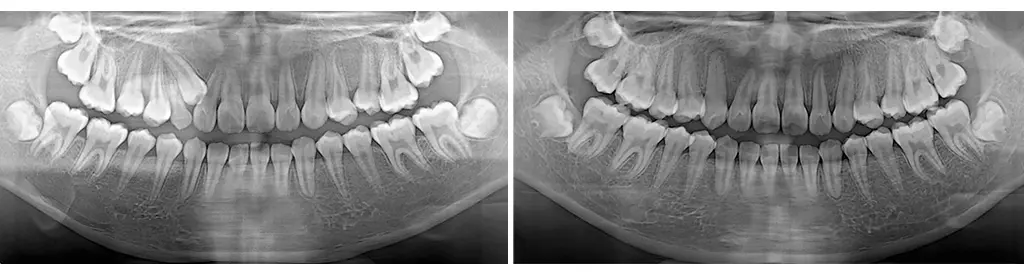

病人小美是國小六年級生,她的乳牙全部都掉完了,唯獨剩下一顆右上乳犬齒。家長原本不以為意,想讓牙齒順其自然生長就好,誰知等了好久好久,這最後一顆乳牙絲毫沒有動搖,不像是會脫落的樣子。更糟糕的是,有一天小美刷牙的時候,發現牙齦上冒出來一坨白白的東西,好像是恆牙長歪了!家長趕緊帶小美來看牙醫。

經過檢查後發現,原來小美的犬齒完全沒有長在應有的位子上,反而從旁邊另闢蹊徑冒出頭來,於是在醫生的安排下進行牙齒矯正治療。首先,要將該掉而未掉的乳牙拔除。由於乳牙的空間不夠容納恆牙,接下來要將空間撐寬,準備好恆牙的位子。最後,在歪掉的犬齒上黏著一個勾勾,請小美每天自己換橡皮筋,把牙齒拉下來。

很快就到了農曆春節,由於吃東西的時候牙套及橡皮筋都要拿下來,小美在家有好多好多東西可以吃,實在沒有空戴橡皮筋。而且放假的時候,玩電腦都玩到很晚,才被家長匆匆忙忙趕上床,有好幾天忘記掛橡皮筋就睡覺了。放完年假之後回診,醫生發現牙齒怎麼沒進步?小美這才知道還是要靠自己的努力,治療才會有用。開學之後,小美超級認真!午餐都會提前五分鐘吃完,去廁所刷完牙,再戴牙套及橡皮筋。於是在畢業典禮後、升國中前的暑假,順利完成矯正治療。